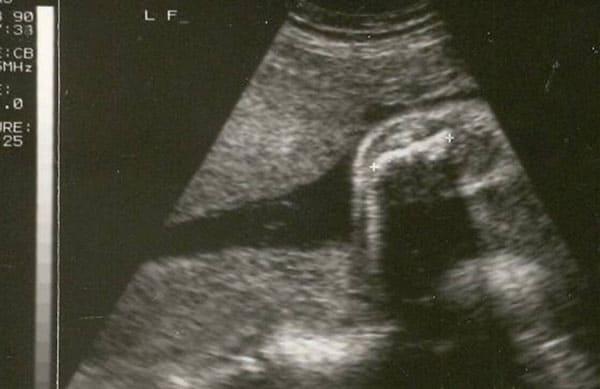

This course provides a detailed understanding of the sonographic detection of severe skeletal dysplasias, focusing on the critical role of early diagnosis in managing pregnancies and genetic counseling. Learn how to identify key markers such as femur length, body proportionality, and other skeletal anomalies to diagnose conditions like achondroplasia, osteogenesis imperfecta, and thanatophoric dysplasia.

Be able to explain why measurement of the femur length often provides the first clue that bone formation is abnormal

Discuss how comparison of femur length with other growing body parts can help confirm skeletal dysplasia

Know how to summarize the remainder of the extended anatomical survey to predict lethality